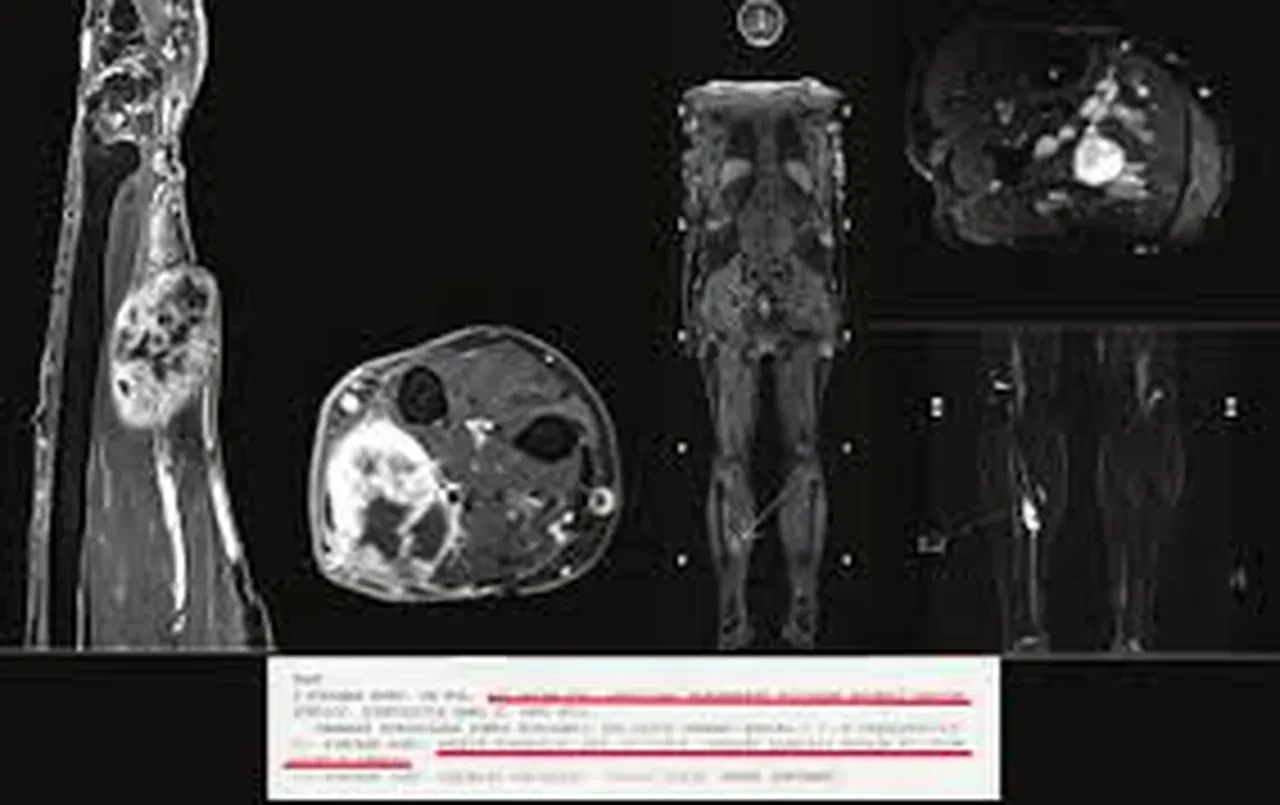

Rabdomyosarkom, kas veya fibröz dokuda gelişen nadir ve agresif bir yumuşak doku kanseridir. En sık 5-9 yaş arası çocuklarda görülür. Uzmanlar, ebeveynlerin çocuklarında fark ettikleri şişlikleri, açıklanamayan yorgunlukları ve mide rahatsızlıklarını ciddiye alması gerektiği konusunda uyarıyor.

Rabdomyosarkom, çocukluk çağında görülen yumuşak doku sarkomlarının en yaygın türüdür.

Erken teşhis edilmediğinde hızla yayılabilir.

Karında görüldüğünde, solunum güçlüğüne kadar ilerleyebilen bası semptomlarına neden olabilir.